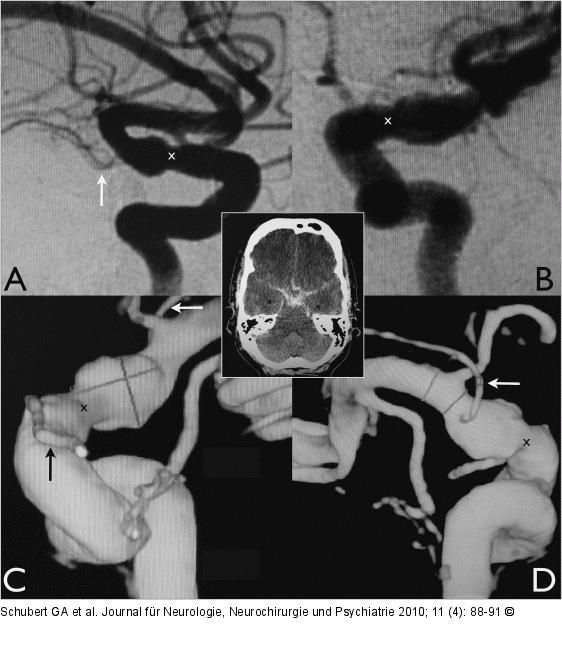

Abbildung 1a-d: Arteria carotis - Aneurysma In der konventionellen digitalen Subtraktionsangiographie (A, B) kann die proximale Stenose (x) unmittelbar vor Beginn der dolichektatischen Erweiterung der ACI nachvollzogen werden. Wird die konventionelle Aufnahme 3-dimensional rekonstruiert (C, D), so ist die Konfiguration des Aneurysmas noch deutlicher ersichtlich. Entscheidend ist hierbei auch das Verhältnis zur A. ophthalmica (schwarzer Pfeil) und der A. choroidea anterior (weißer Pfeil), welche in unmittelbarer Nähe des Aneurysmas ihren Ursprung haben und bei einer chirurgischen Versorgung zwingend geschont werden müssen. |

In der konventionellen digitalen Subtraktionsangiographie (A, B) kann die proximale Stenose (x) unmittelbar vor Beginn der dolichektatischen Erweiterung der ACI nachvollzogen werden. Wird die konventionelle Aufnahme 3-dimensional rekonstruiert (C, D), so ist die Konfiguration des Aneurysmas noch deutlicher ersichtlich. Entscheidend ist hierbei auch das Verhältnis zur A. ophthalmica (schwarzer Pfeil) und der A. choroidea anterior (weißer Pfeil), welche in unmittelbarer Nähe des Aneurysmas ihren Ursprung haben und bei einer chirurgischen Versorgung zwingend geschont werden müssen. |